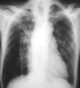

Melioidosis is an infectious disease caused by a Gram-negative bacterium called Burkholderia pseudomallei. Most people infected with B. pseudomallei experience no symptoms, but those who do experience symptoms have signs and symptoms that range from mild, such as fever, skin changes, pneumonia, and abscesses, to severe with inflammation of the brain, inflammation of the joints, and dangerously low blood pressure that causes death. [Source: Wikipedia ]